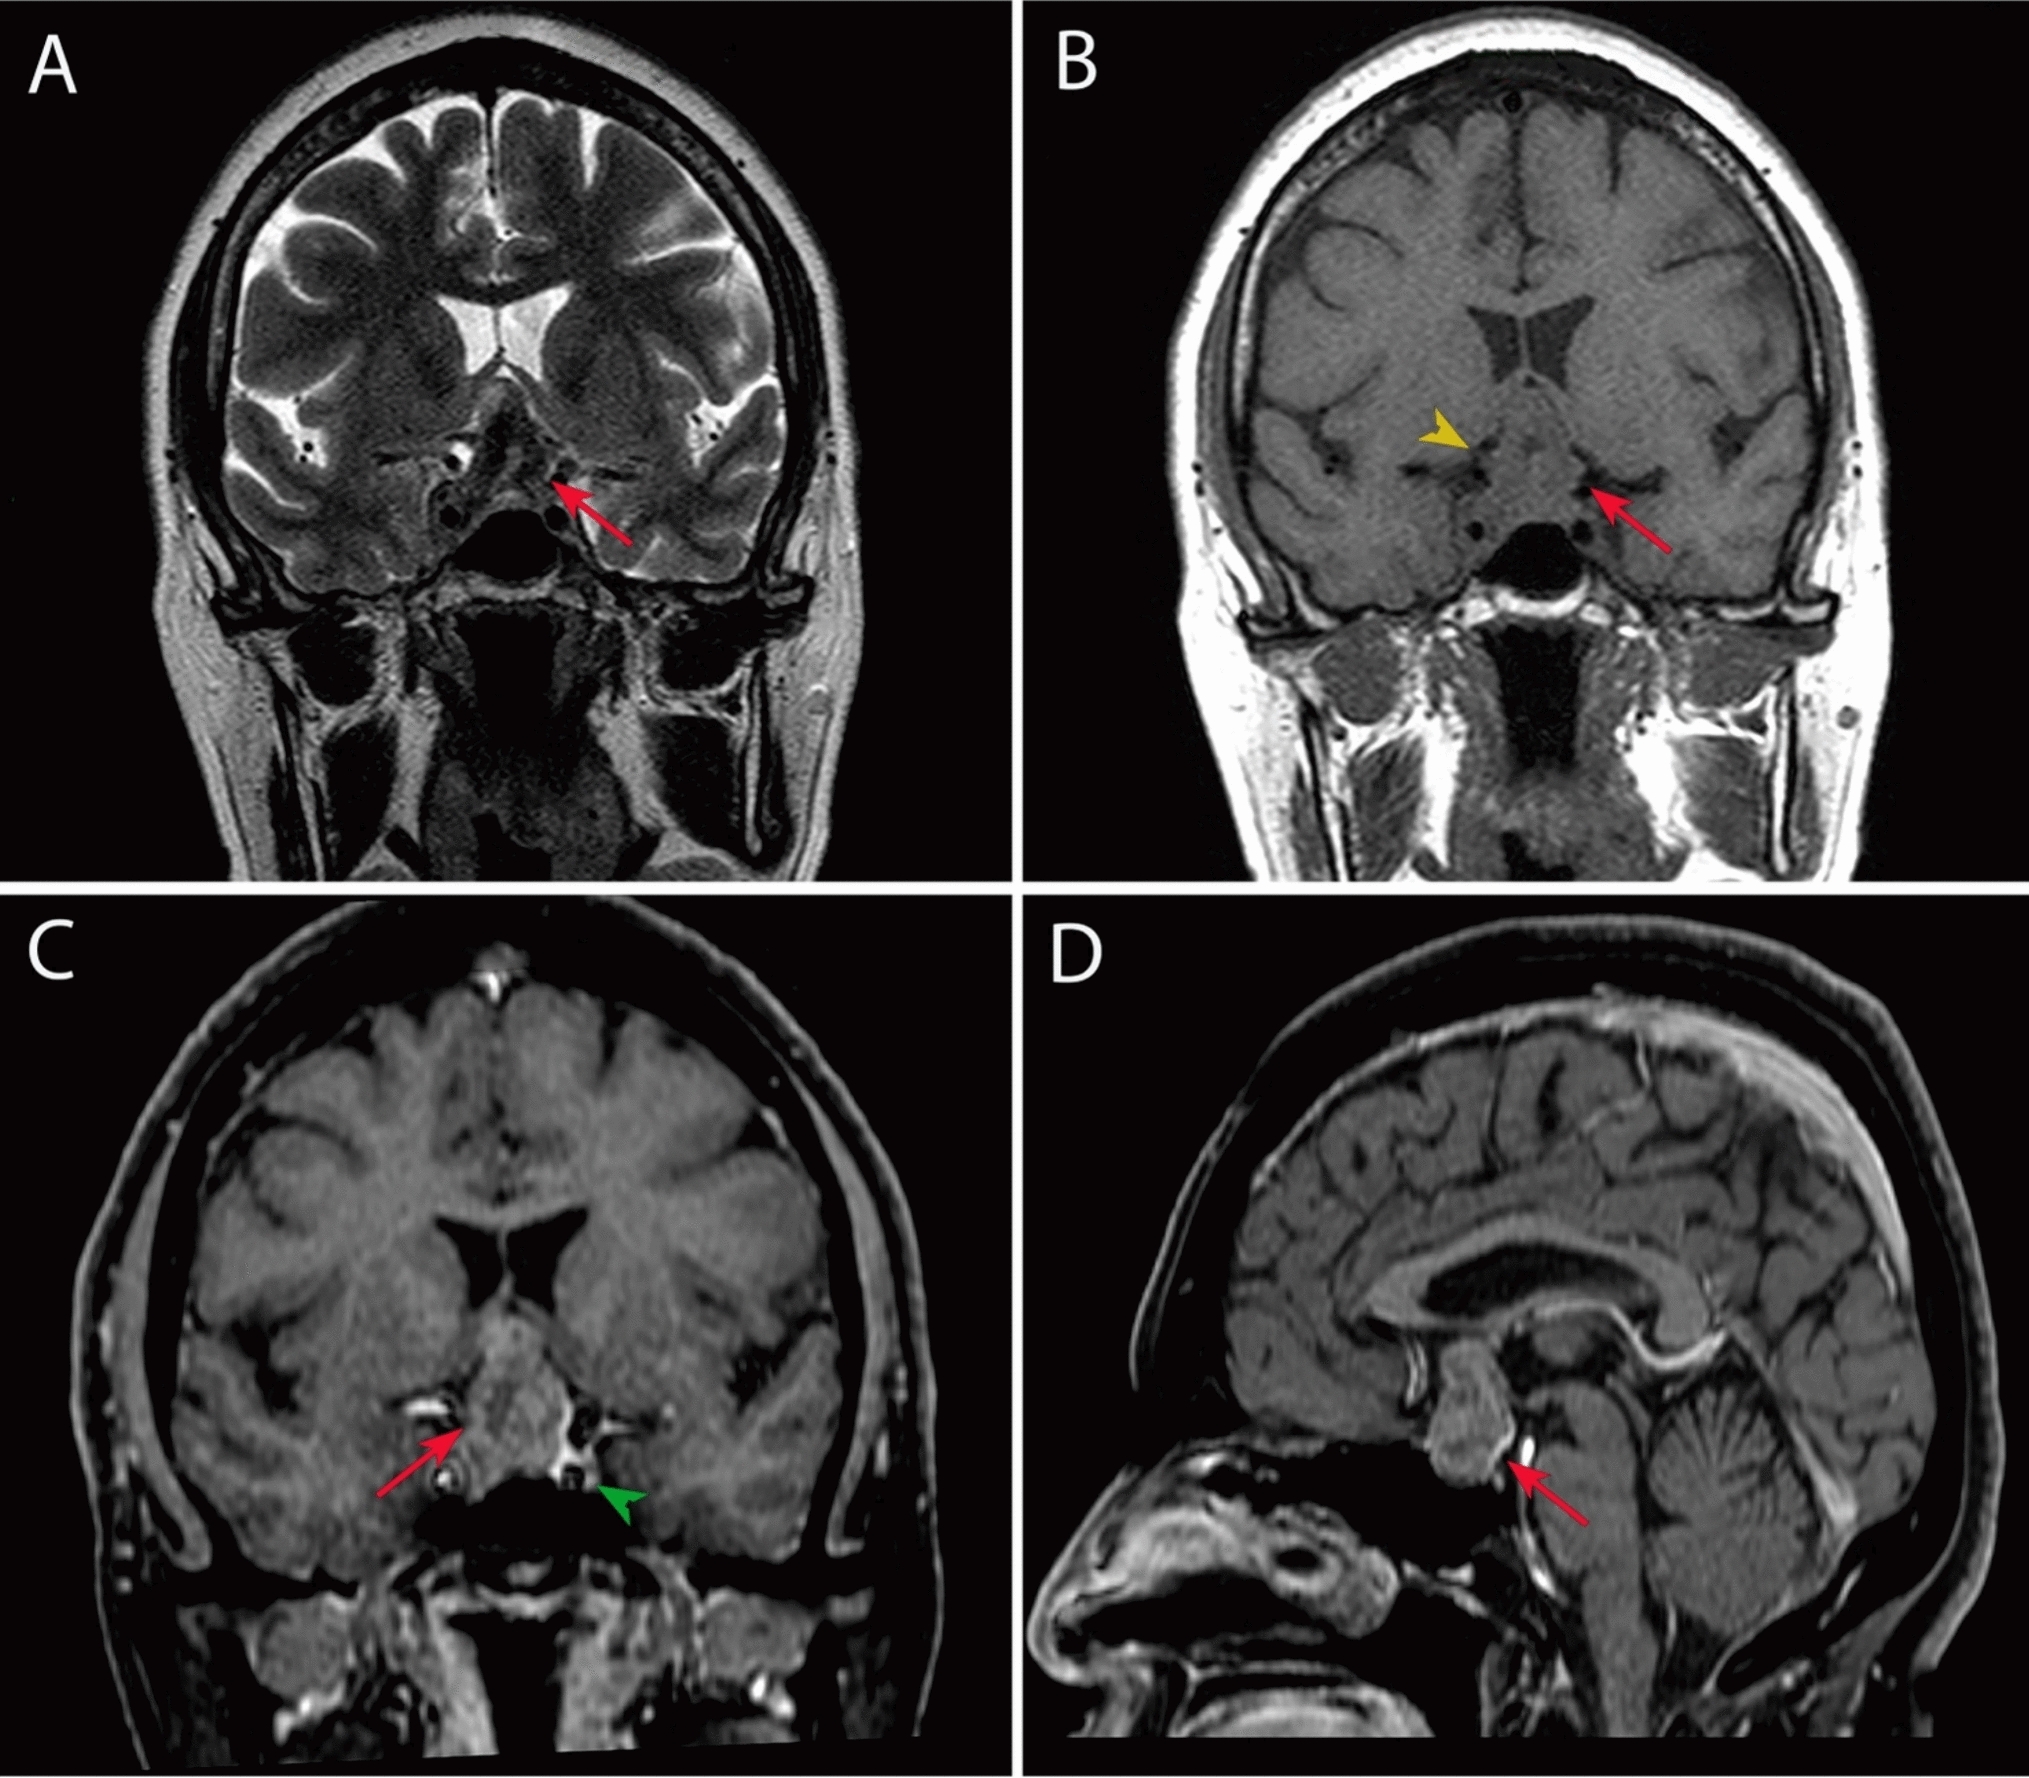

Figure 3 illustrates each patient’s clinical course, including preoperative radiologic imaging.

Fig. 3figure 3

Illustration of patient’s clinical course, including preoperative MR-imaging. ADM adriamycin, CCNU lomustine, CTX cyclophosphamide, DWI diffusion-weighted imaging, Gd gadolinium, Gy gray, MRI magnetic resonance imaging, n native, OS overall survival, PFS progression-free survival, RCTX radiochemotherapy, RTX radiotherapy, T1w T1 weighted, T2w T2 weighted, TMZ temozolomide, VCR vincristine, y years

A 52-year-old female patient was admitted to our hospital with the chief complaint of severe headache. MRI demonstrated a T1 hypointense and FLAIR hyperintense bithalamic lesion (right > left) with no contrast-enhancement (see Fig. 3O, P). In July 2022, a stereotactic biopsy was performed. DNA-methylation analysis showed a diffuse paediatric-type high-grade glioma, H3-wildtype and IDH-wildtype, subtype A&B (v12.5 classifier score 0.96). Immunohistochemical stains with antibodies against H3 K27M and H3 p.27me3 were performed during routine diagnostics. H3 K27M mutation was not present and H3 trimethylation was retained. A TERT promoter C228T mutation was detected by Sanger sequencing. Next-generation sequencing using the Illumina TruSight Oncology (TSO500) Panel revealed two additional, likely pathogenic mutations (BCOR c.4050C > A; p.Y1350 [NM_001123385.1]; CREBBP c.4337G > A; p.R1446H [NM_004380.2]) and an EGFR exon 18–25 kinase domain duplication (EGFR-KDD). Interdisciplinary tumor board recommended radiochemotherapy and TTF. Further treatment took place at an external hospital where it was agreed to postpone radiochemotherapy and try a watch and scan approach as the patient had no clinical signs of disease (Karnofsky performance score (KPS) 100%). MRI from November 2022 showed no tumor progression. The patient was alive at the last follow-up, four months after the initial diagnosis.